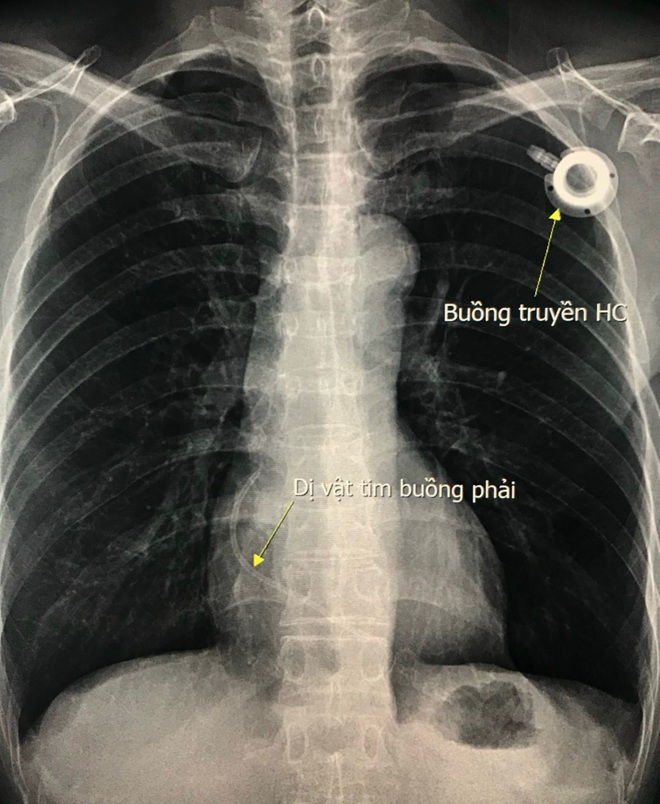

(Dân trí) - 6 năm trước, kết thúc liệu trình điều trị ung thư vú, người bệnh không lấy buồng truyền hóa chất ra ngoài. Tháng 11/2021, dây nối của buồng truyền bị đứt, trôi theo mạch máu, bị kẹt lại ở trong tim.

Trước đó, năm 2015, khi phát hiện ung thư vú, bệnh nhân được phẫu thuật và đặt buồng truyền hóa chất để điều trị hóa chất bổ trợ. Sau khi kết thúc liệu trình điều trị, do e ngại việc phải phẫu thuật can thiệp nhiều lần nên người bệnh đã không lấy buồng truyền ra. Đến tháng 11/2021, sau 6 năm, dây nối của buồng truyền bị đứt và trôi theo mạch máu và bị kẹt lại ở trong tim.

Dị vật kẹt trong tim được lấy ra.